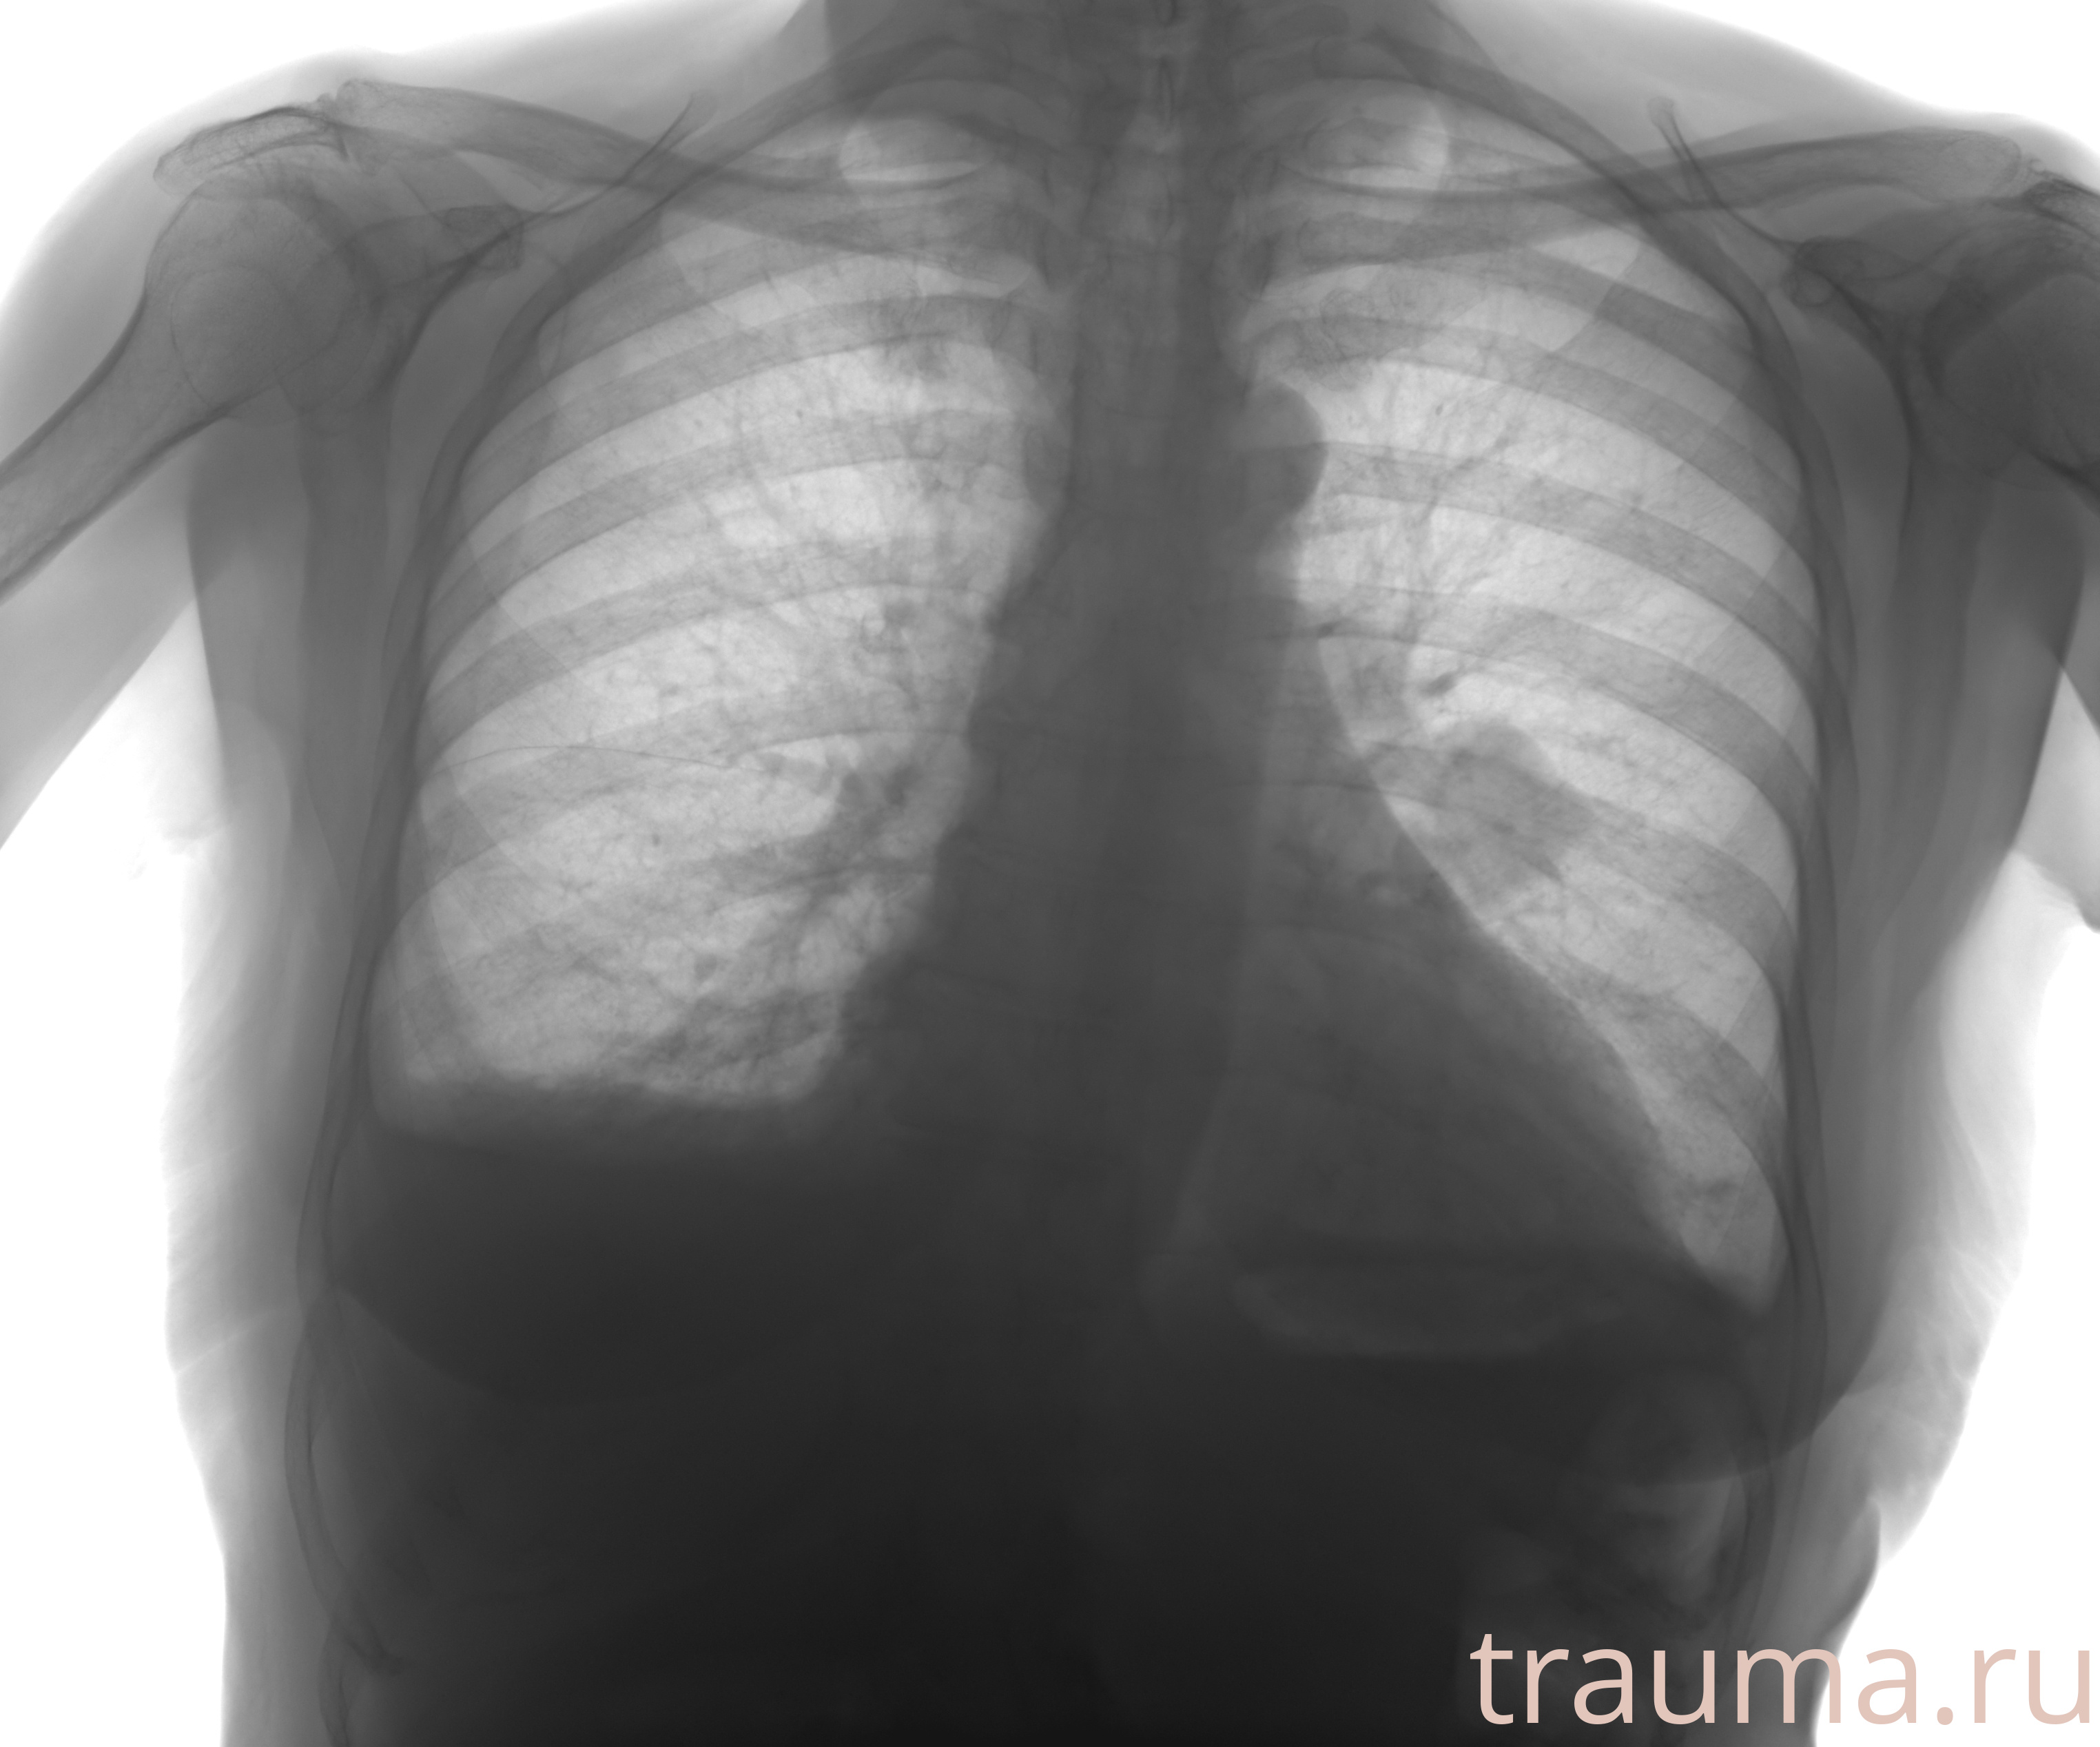

Рентгенограммы

Натуживание 26.12.2025 21:16:34